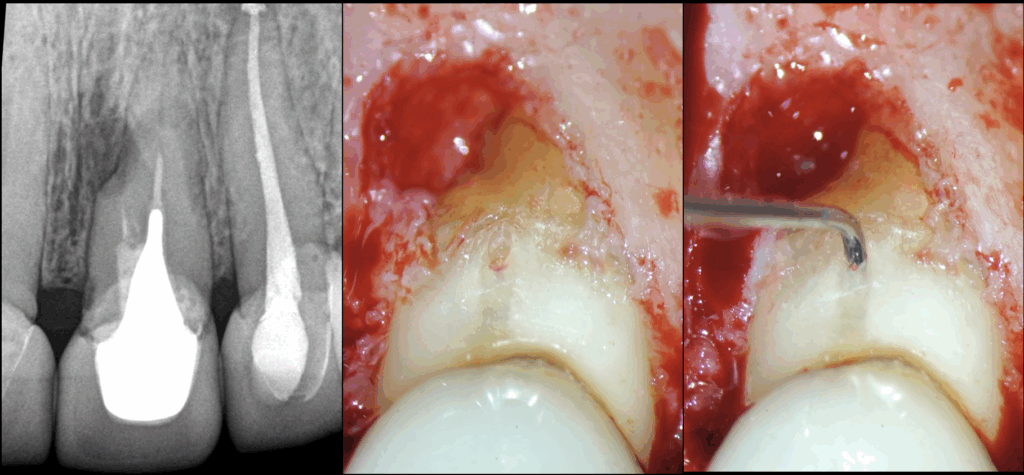

🔍 Chirurgie endodontique de 21 22

🦷 𝐋𝐚 𝟐𝟏 𝐧𝐨𝐮𝐬 𝐢𝐧𝐭𝐞́𝐫𝐞𝐬𝐬𝐞 𝐩𝐚𝐫𝐭𝐢𝐜𝐮𝐥𝐢𝐞̀𝐫𝐞𝐦𝐞𝐧𝐭 𝐢𝐜𝐢

👉 Pour sa résorption radiculaire externe

👉 Pour ses fausses routes

🔬 𝐋𝐞𝐬 𝐩𝐨𝐫𝐭𝐞𝐬 𝐝𝐞 𝐬𝐨𝐫𝐭𝐢𝐞𝐬 𝐜𝐚𝐮𝐬𝐚𝐧𝐭 𝐥𝐞𝐬 𝐫𝐞́𝐚𝐜𝐭𝐢𝐨𝐧𝐬 𝐢𝐧𝐟𝐞𝐜𝐭𝐢𝐞𝐮𝐬𝐞𝐬 / 𝐢𝐧𝐟𝐥𝐚𝐦𝐦𝐚𝐭𝐨𝐢𝐫𝐞𝐬 𝐬𝐨𝐧𝐭 𝐩𝐫𝐞́𝐩𝐚𝐫𝐞́𝐞𝐬 𝐚 𝐫𝐞𝐭𝐫𝐨 𝐞𝐭 𝐨𝐛𝐭𝐮𝐫𝐞́𝐞𝐬 𝐚𝐮 𝐜𝐢𝐦𝐞𝐧𝐭 𝐛𝐢𝐨𝐜𝐞́𝐫𝐚𝐦𝐢𝐪𝐮𝐞.